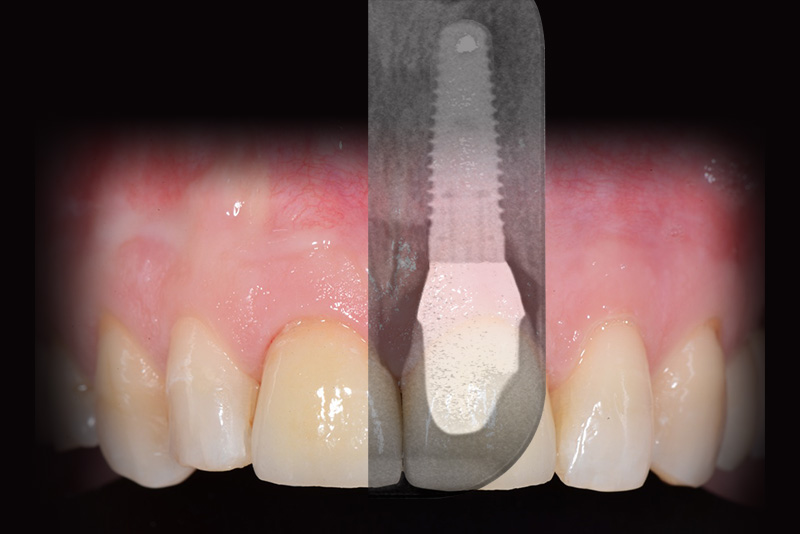

PREMESSA: in seguito all’estrazione dell’incisivo laterale superiore di destra, resasi necessaria per cause batteriche, si decide di affrontare il caso con il posizionamento di un impianto in sostituzione dell’elemento mancante dopo guarigione del sito infetto. Con tecniche rigenerative sia dei tessuti ossei mancanti a causa dell’infezione pregressa, sia dei tessuti gengivali che appaiono inizialmente troppo spostati in alto, si ripristina una corretta morfologia delle parabole (contorni) gengivali e delle papille interdentali (triangoli di gengiva tra due denti vicini).

Vengono utilizzati 2 tipi di provvisori: il primo, cementato ai denti vicini, viene utilizzato dal momento dell’estrazione del dente fino ad impianto osteointegrato (circa 6 mesi); il secondo, avvitato direttamente all’impianto, ha una funzione di prova estetica ma soprattutto di guida per la maturazione dei tessuti gengivali peri-implantari portandoli verso la maturazione completa prima di posizionare la corona finale in disilicato di litio.